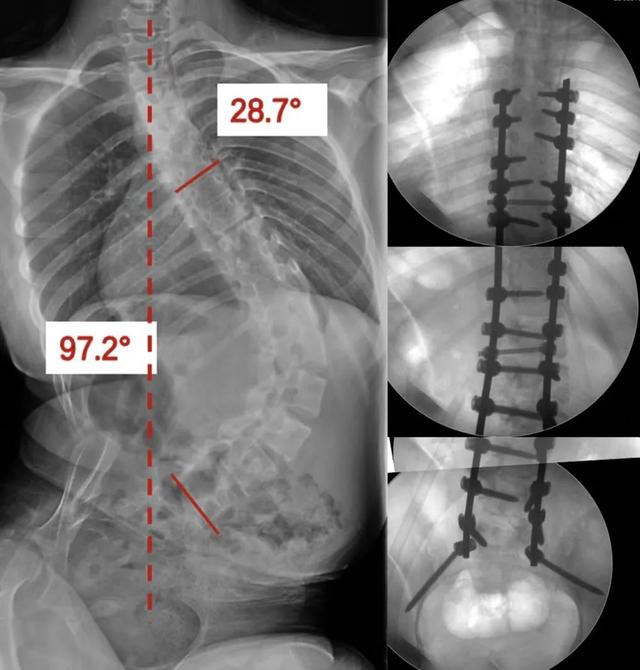

姗姗术前脊柱全长X线

朝阳骨科脊柱团队术前规划

术后透视(右)与术前(左)脊柱对比